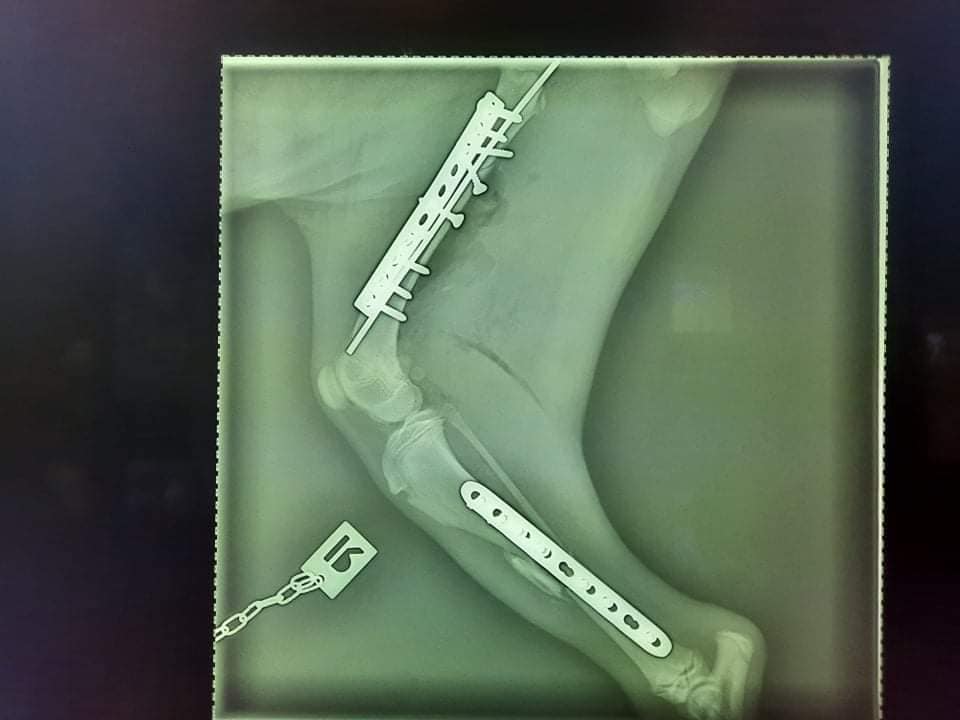

V sobotu večer 29.1.2022 sme dostali telefonát od mladého muža, ktorý našiel na hlavnej ceste v obci Markušovce zrazeného psíka. Okamžite kontaktoval políciu aj nás. Vyrazili sme na miesto, kde nás čakali chalani spolu s políciou. Na ceste ležala zranená fenka, ktorú prikryli dekou, keďže vonku bola zima. Odviezli sme ju rovno na kliniku a dali jej meno Melka. Vyšetrenia odhalili štyri zlomeniny na troch nôžkach, pričom jedna zo zadných bola veľmi vážne poškodená a zlomená bola aj jedna predná labka. Melka bola prevezená do nemocnice Marfilvet v Bratislave, kde jej bohužiaľ diagnostikovali parvovirózu. Začal sa boj o jej život aj záchranu nôh. Napriek všetkému to úžasná bojovníčka Melka zvládla.